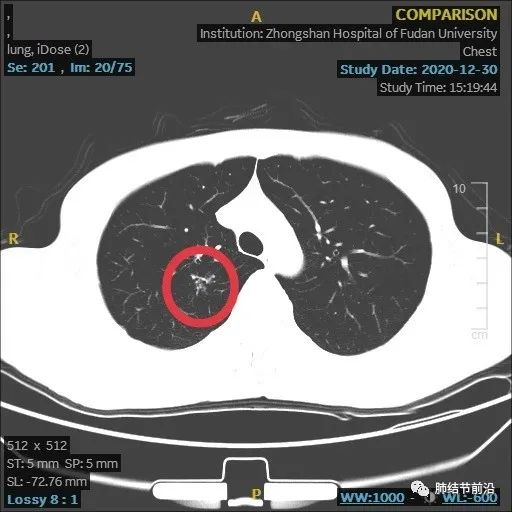

患者之后再复查,果然结节大部分吸收。

本病例显示了炎症性结节的发展过程,由8mm实性结节,变成了14mm的多中心堆积结节,后面又自行吸收。炎症为何种病菌感染,无法肯定,该结节也有结核可能。

多中心堆积结节,多考虑炎症肉芽肿,如果病灶中随访慢慢变实性,再考虑为腺癌。应注意影像特点,避免误切。